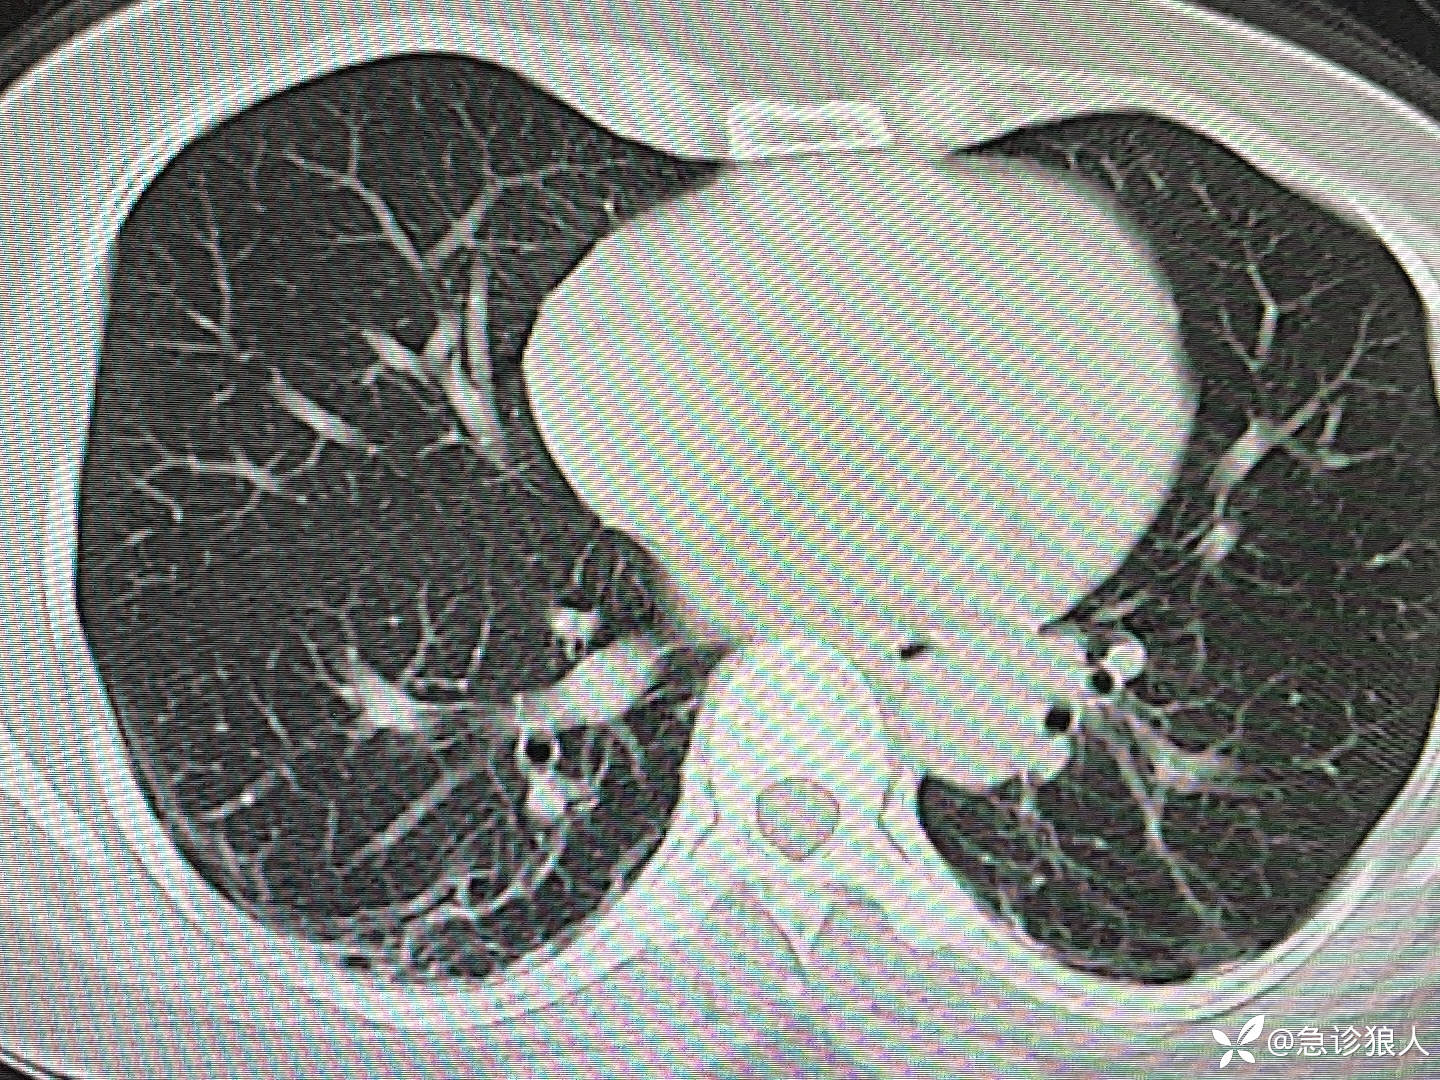

入院12小时,胸部CT如下:

入院第4天,血检全正常,ct如下: